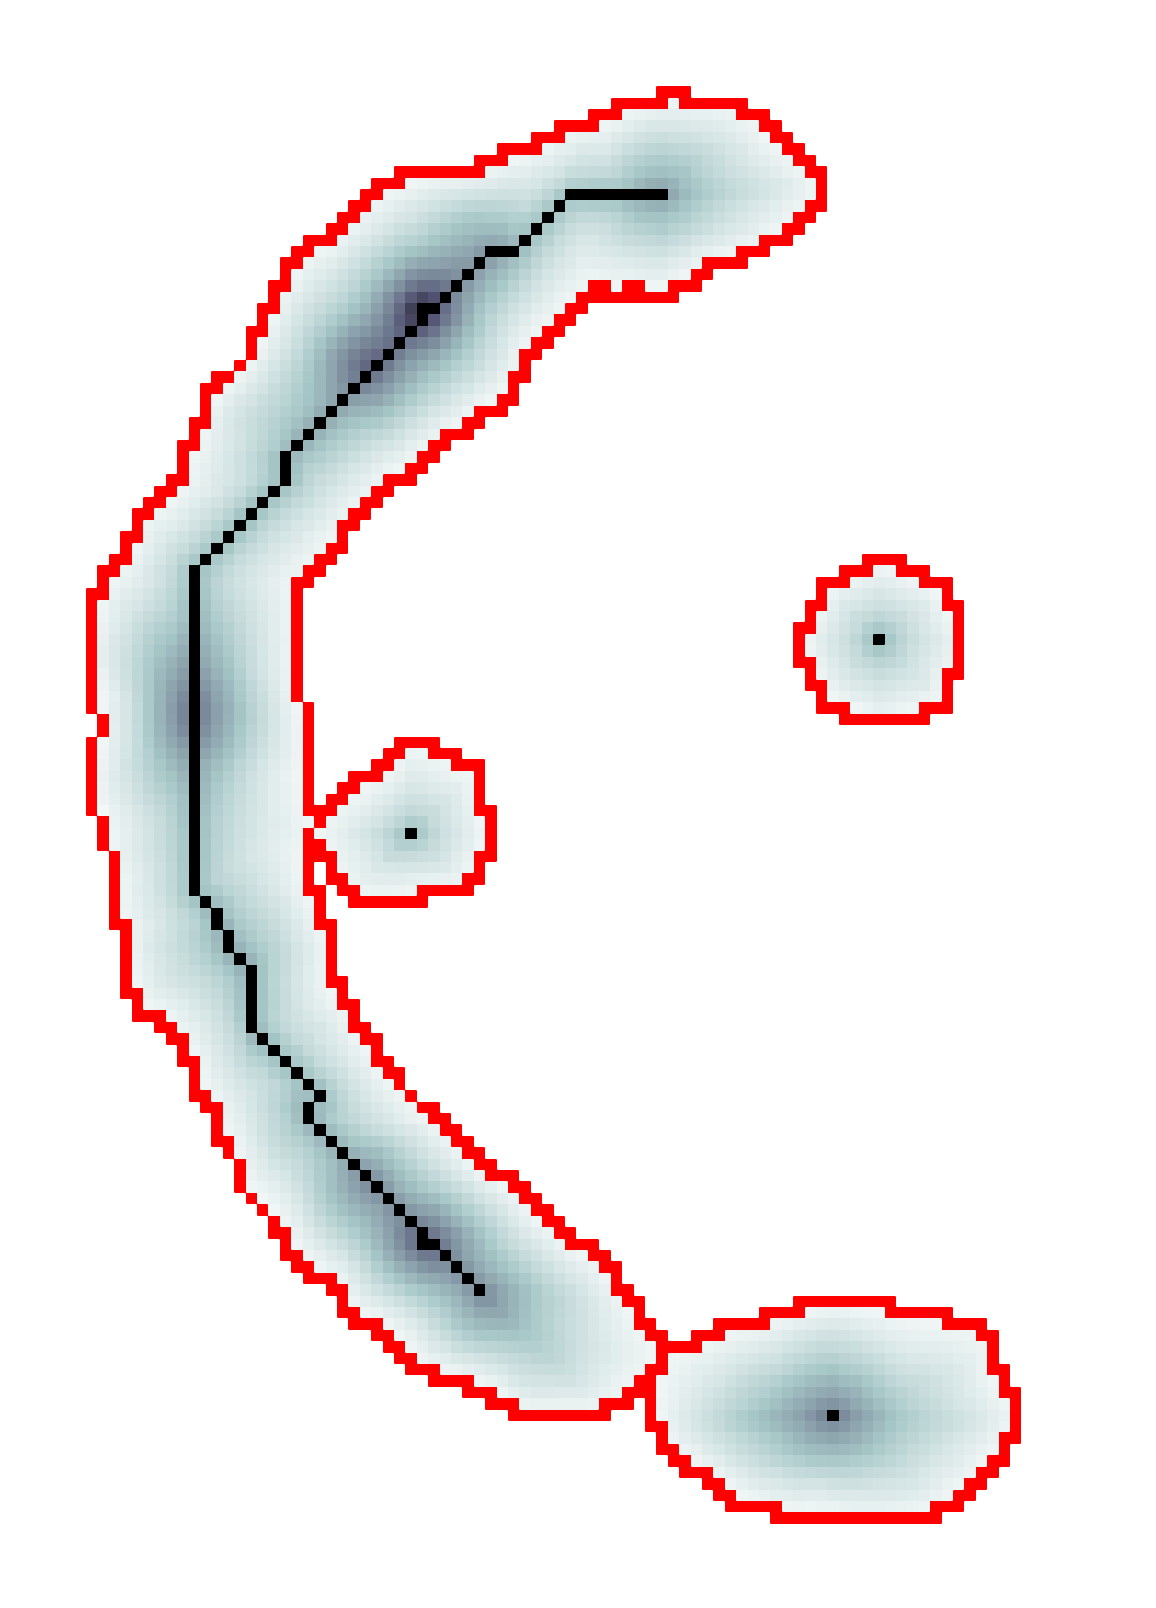

The scalar vesselness responses of both HCP and PC images are determined using the state-of-the-art Frangi filter (FFR) [8], and Optimally Oriented Flux (OOF) [12]. Also, the connected vesselness map (CVM) and the associated tensor field (TF) are synthesized for the same dataset using VTrails. The connectedness of the considered scalar maps is qualitatively assessed and the TF is inspected as proof of concept in section 3.1.

3.1 Connectedness of the Vesselness Map

Fig. 3 shows the connectedness of vessels recovered from state-of-the-art vascular enhancers and curvilinear ridge detectors FFR and OOF together with the proposed CVM for the synthetic HCP and the real PC images.

On the synthetic phantom, FFR shows a fragmented and rough vesselness response in correspondence of irregularly shaped sections of the structure. Also, the response at the bifurcation is not smoothly connected with the branches (triangular loop). Conversely, OOF recovers the phantom connectedness at the branch-point, and the vesselness response is consistent along the tortuous curvilinear section, however ghosting artifacts are observed as the shape of the phantom becomes irregular (C-like) or differs from a cylindrical tube. Also, close convoluted structures, which change scale rapidly in the HCP, produce inconsistent responses of OOF (fig. 3). CVM shows here a strongly connected vesselness response in correspondence of both regular and irregular tubular sections, with local maxima at structures’ mid-line. The connectedness of the structures is emphasized regardless the complexity of the shape, and it resolves spatially the tortuous curvilinear ‘kissing vessels’ without additional ghosting artifacts, despite the smooth profile.

Similar results are observed on the PC dataset: FFR has a poor connected response in the noisy and low-resolution image. Vessels are overall enhanced, however thin and fragmented structures remain disconnected. Overall, the vesselness response is not uniform within the noisy structures, where maximal values are often off-centred. A more consistent response is obtained from OOF, where the connectedness of vessels is improved. Maximal response is observed at the mid-line of vessels, however, noise rejection is poor. CVM strongly enhances here the vessel connectivity. The fragmented vessels of PC have a continuous and smooth response in CVM with higher values and a more defined profile. Large vessels shows solid connected regions with local maxima at mid-line as in OOF. Conversely from OOF, CVM shows improved noise rejection in the background.

The respective tensor fields (TF) synthesized on both HCP and PC show consistent features. The TF’s characteristics are in line with the connectedness of CVM: enhanced and connected vessels are associated with high anisotropy, whereas background areas show a predominant isotropic component.